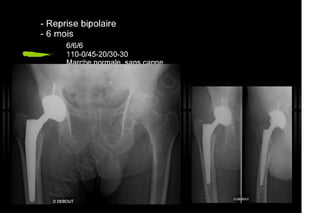

2013 032. Douleur sur PTH céramique-céramique

032. Douleur sur PTH céramique-céramique - Painfull THA with Alumine-Alumine bearing